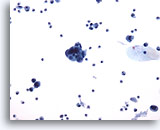

Figure 50

Urine, low grade carcinoma

Cells of low grade urothelial carcinoma may be in small groups with some single cells. 20x

Urine, low grade carcinoma

Cells of low grade urothelial carcinoma may be in small groups with some single cells. 20x

Figure 50

Urine, low grade carcinoma

Cells of low grade urothelial carcinoma may be in small groups with some single cells.

20x

Urine, low grade carcinoma

Cells of low grade urothelial carcinoma may be in small groups with some single cells.

20x